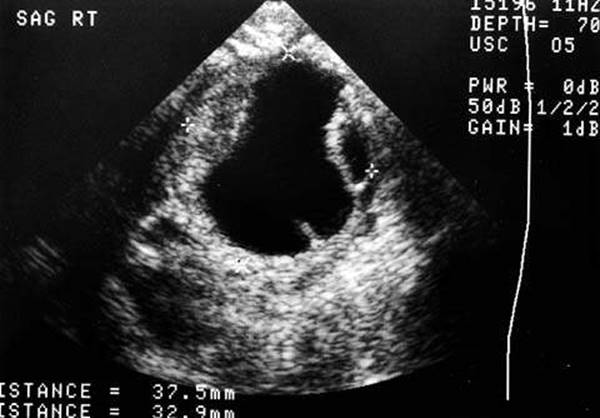

Figure 14.7 Pelvic ultrasound (transabdominal) of a premenarchal 10-year-old girl.

Imaging

If an ovarian or vaginal mass is suspected, a transabdominal pelvic ultrasonographic examination can provide useful information. The appearance of the ovaries (normal prepubertal size and volume, follicular development, cystic, or solid) can be noted, as well as the size and configuration of the uterus. The prepubertal uterus has a distinctive appearance, with equal proportions of cervix and fundus and a size of approximately 2 to 3.5 cm in length and 0.5 to 1 cm in width (Fig. 14.7). The uterine fundus enlarges with estrogen stimulation, resulting in the postmenarchal appearance in which the uterine fundus is larger than the cervix (19). An ultrasonographic examination should be the first imaging study performed; more sophisticated imaging techniques, such as magnetic resonance imaging (MRI) or computed tomography (CT) scanning, are rarely indicated as initial diagnostic modalities, and they add unnecessary expense and radiation exposure with CT.